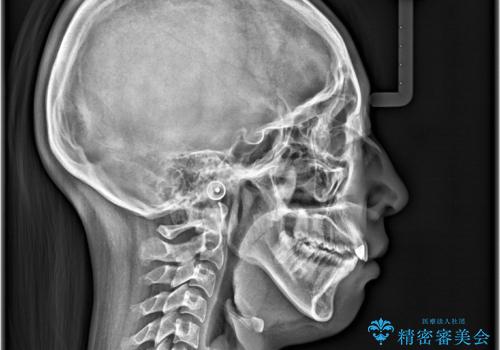

- 歯のデコボコと右上2番の歯の形が気になることを主訴に来院された患者様です。

軽度の叢生(凸凹)であったため、インビザラインのライトパッケージを用いて歯並びを改善しました。その後、右上2番はオールセラミッククラウンにより形態を回復し、審美性を向上させました。